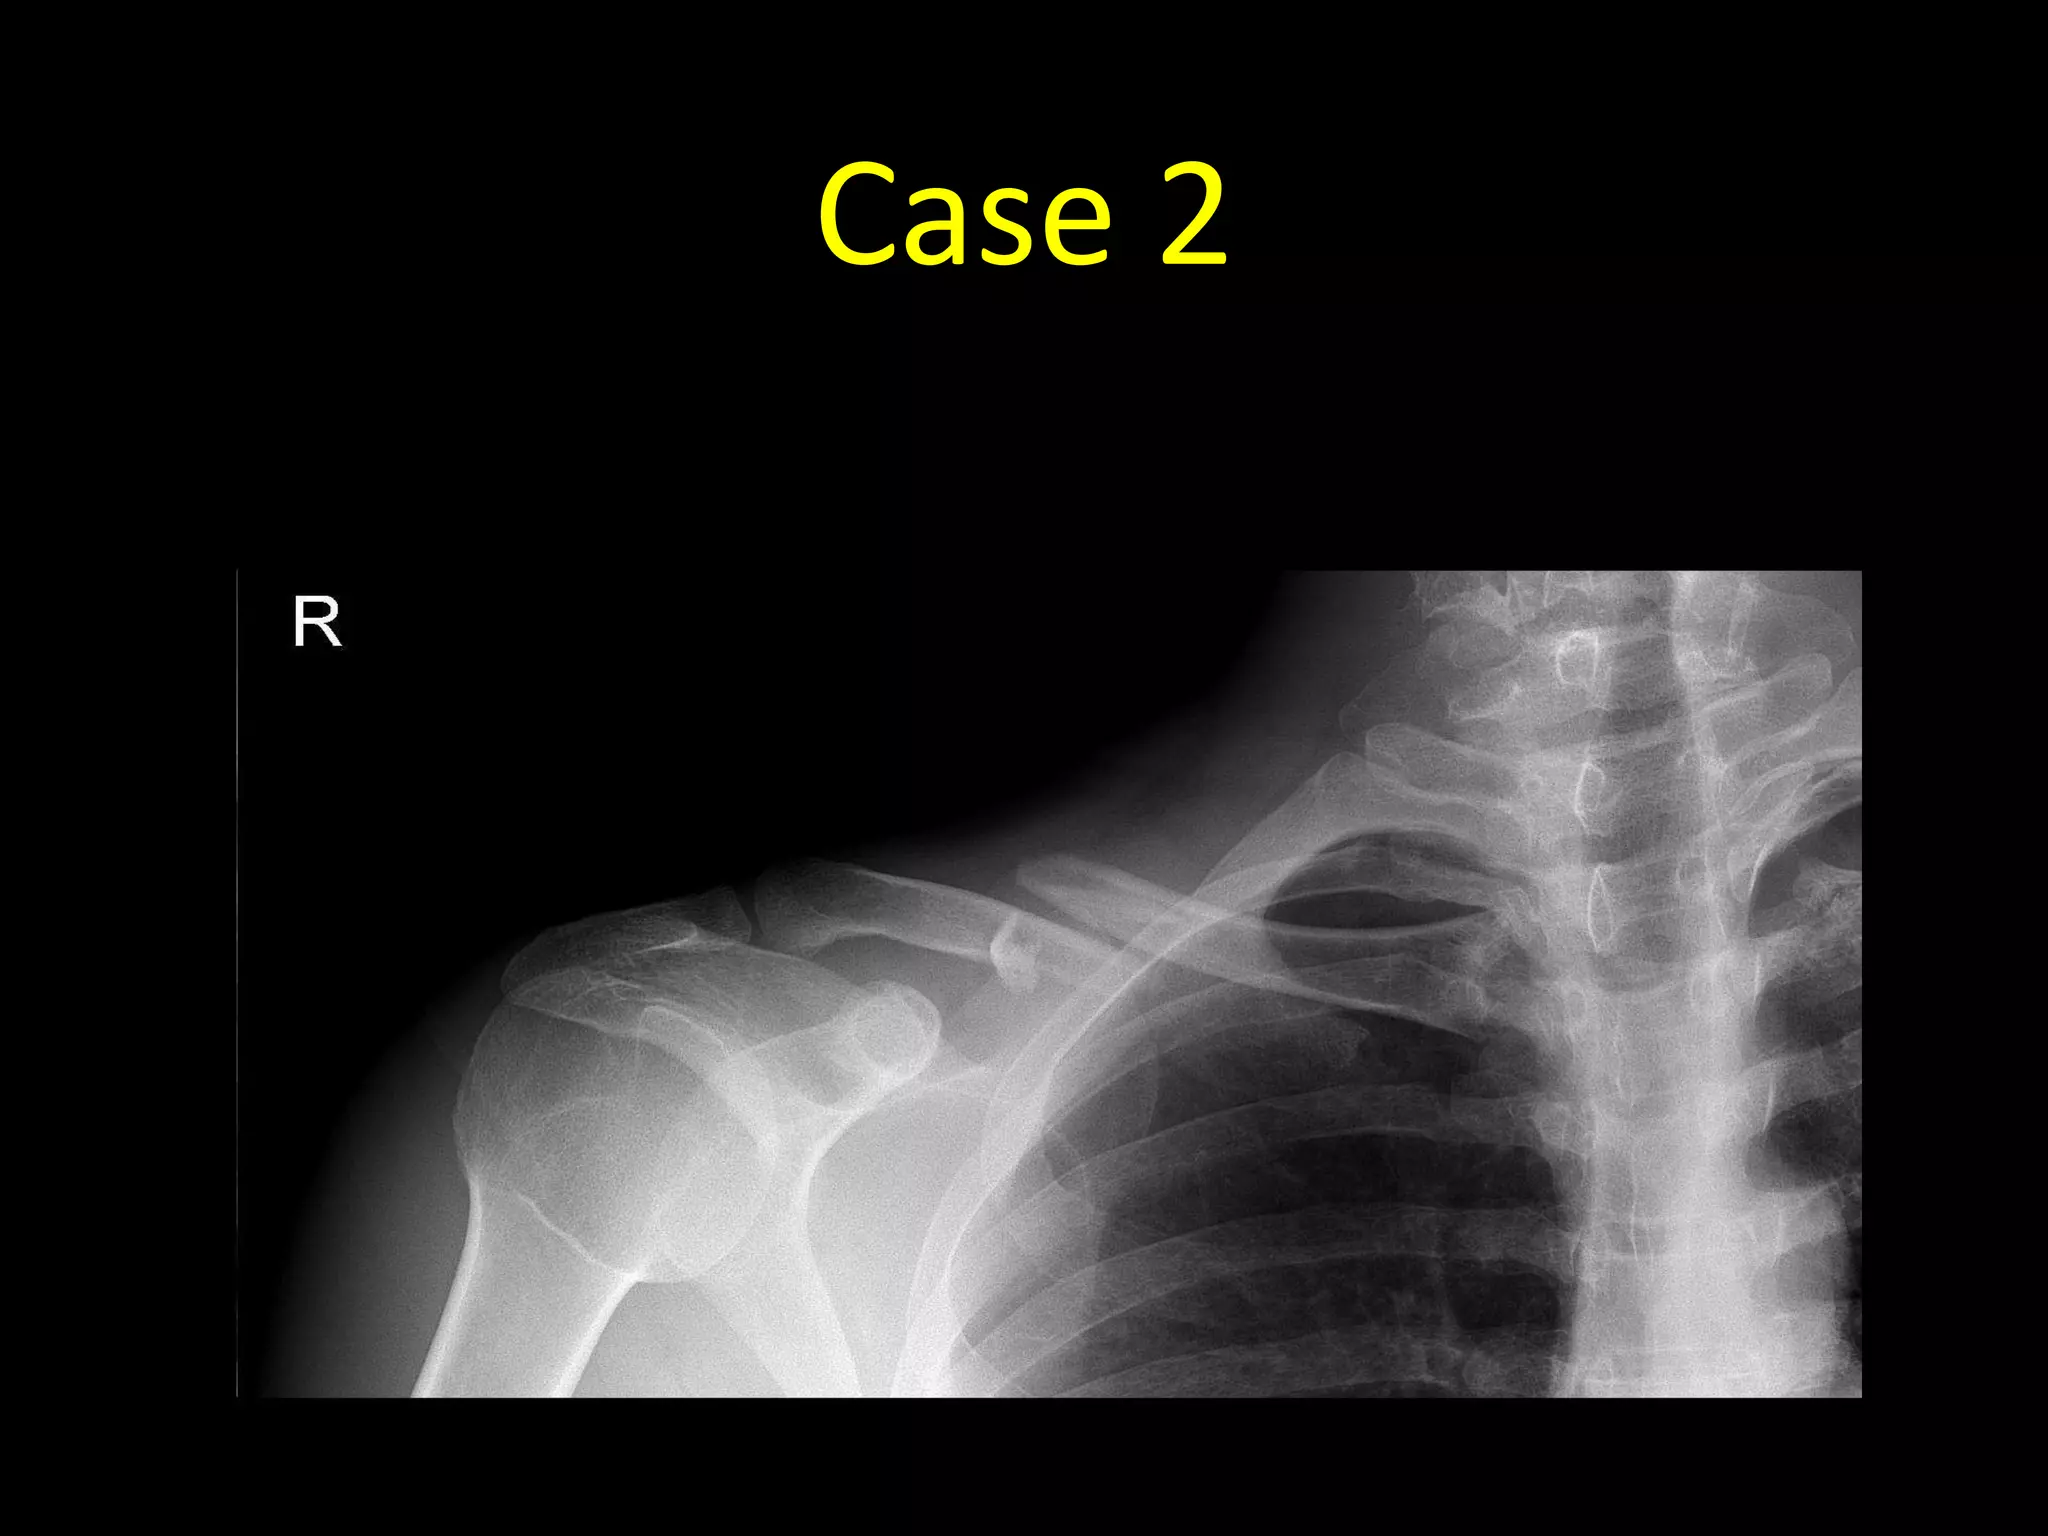

Case 2

• 27 year old with pain in the right shoulder after a

sports injury

• AP radiograph of the right

shoulder

• There is a completely

displaced comminuted

fracture of the right clavicle at

the junction of the middle

and lateral thirds

• The fracture is described as

comminuted as there are

three separate fracture

fragments (arrows)